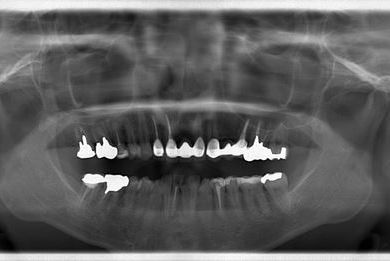

| 性別/年齢 | 女性 / 40歳 | ||||||||||||||||||||||||||||||||

| 主訴 | 前歯のさし歯の部分が目立ってしまい、新しくしたい。痛みも少しある。 | ||||||||||||||||||||||||||||||||

| 治療方針 | 保存不能な歯を抜歯し、セラミック治療にて、機能的・審美的回復を行う。 | ||||||||||||||||||||||||||||||||

| 治療内容 | ジルコニアフレームオールセラミッククラウン7本(オールセラミック用土台3本)、ハイブリッドセラミッククラウン1本、ハイブリッドセラミックインレー1本 | ||||||||||||||||||||||||||||||||

| 治療部位 |